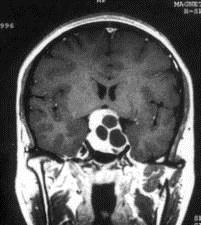

问题 病历摘要:??患者男性,35岁。性功能减退2年,视力下降6月。既往体健。体检:神清,皮肤细腻,毛发稀疏。视力左眼0.3,右眼0.5,双瞳等大等圆,直径3.5mm,对光反射稍迟钝,双颞侧偏盲,双眼底视神经乳头原发性萎缩,余神经系统未见异常。 关于鞍区周围的神经血管间隙的叙述哪些是正确的?